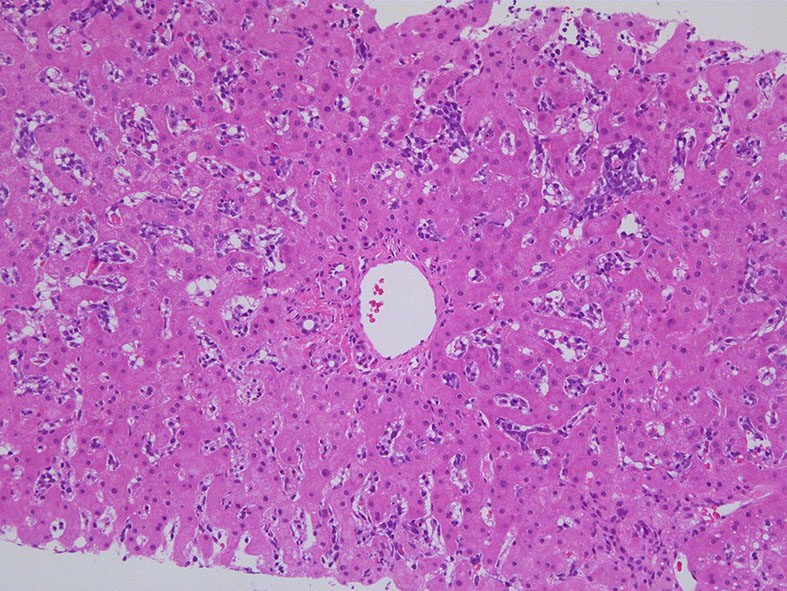

肝臓  サムネイルのクリックで大きな画像が見られます.

肝針生検組織; 類洞に細胞浸潤が認められ, 非浸潤部との境界がぼんやりと認められる. 類洞と異なり, グリソン鞘は腫瘍細胞の浸潤が乏しいか, ほとんど認められない.

類洞内に浸潤増殖するリンパ腫細胞: 類円形・長円, 瓜状の核をもつ,細胞質の乏しい細胞(サムネイル画像のクリックで大きな画像が見られます)